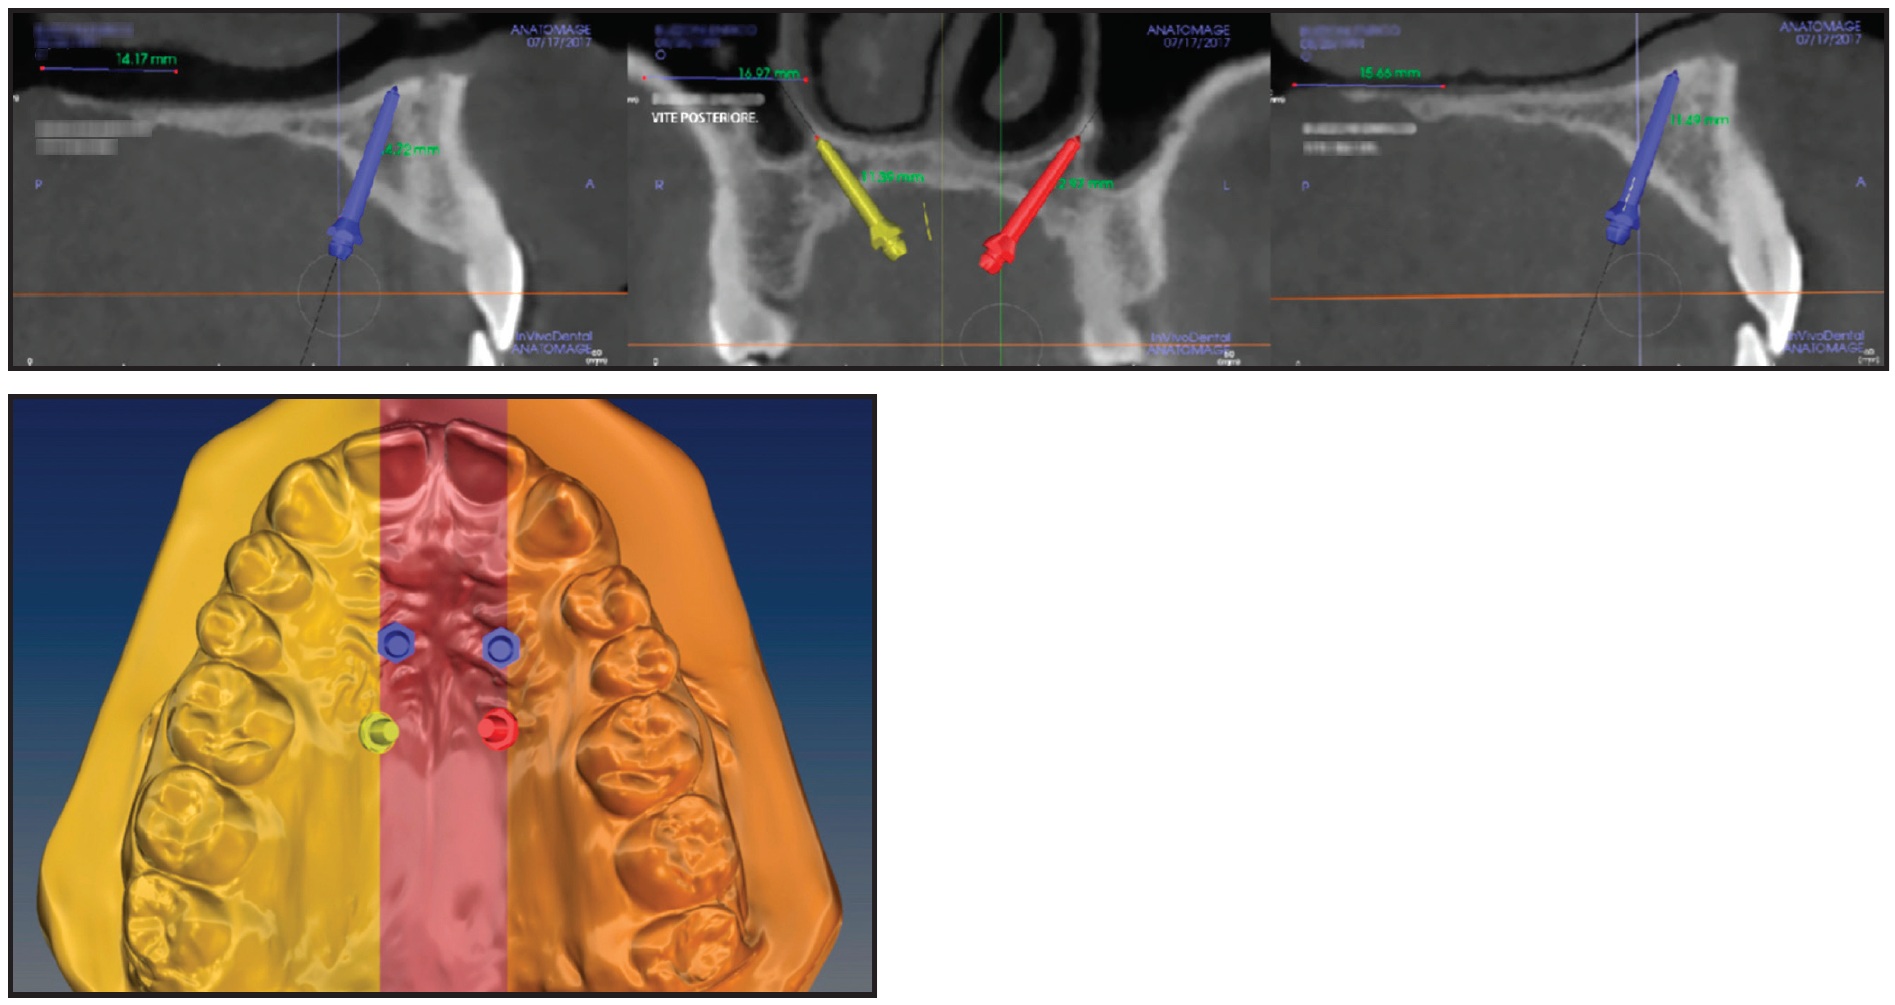

A two-phase treatment was planned using skeletal maxillary expansion to obtain orthopedic correction of the transverse deficiency, followed by dental alignment. The optimal site for miniscrew insertion was identified on the CBCT scan and superimposed onto the stereolithographic (STL) image of the digital model (Fig. 3). The anteroposterior insertion sites were selected based on the thickness and width of the palatal vault. A 3D surgical guide, properly fitting the morphology of the palate, was then printed using the MAPA System.

Fig. 3 Case 1. Virtual planning of miniscrew insertion sites based on Digital Imaging and Communication in Medicine (DICOM) and stereolithographic (STL) files.

A TSE was fabricated from a polyvinyl siloxane impression of the upper arch and a digital design (Fig. 4).

Fig. 4 Case 1. Digital design and placement of TSE.